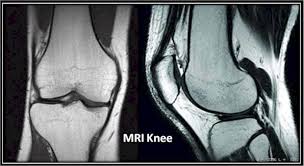

Leave time for filling out paper work and getting dressed for the scan as well. The knee mri can take 30 minutes to an hour. Slices must be sufficient to cover the whole lower leg anterior to posterior. In other cases, it might take a few days. Most knee mri scans take about 30 minutes,. Meet scott, a technologist for michigan residence imaging. Diagnostic radiology 42 years experience. The images can be stored on a computer or printed on film. A patient with knee pain may undergo an mri to enable a doctor to make a diagnosis. How long does it take to get mri results? In some situations, you may get your mri scan results back in as little as a few hours. Specifically for a knee mri, you will likely go in feet first and can generally expect the lower half of your body to be inside of the tube. The test most often lasts 30 to 60 minutes, but may take longer.

Expect to hold still for around 15 to 45 minutes, sometimes longer, while the machine makes images of your. An appropriate angle must be given in the axial plane (parallel to the right and left shaft of tibia). A doctor is trained for over 11 years (many specialists are trained even longer) to make the right decisions on behalf of patients. Does involuntary knee spams interfere with the scan? We scan axial (top to bottom) sagittal (right to left) and coronal (front to back).